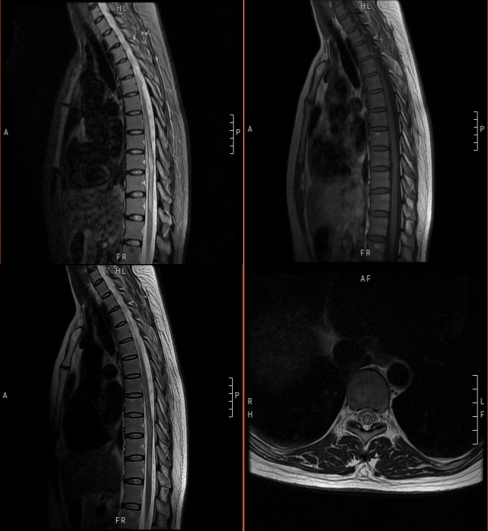

病例1

患者女,41岁。突发双下肢无力6小时。

答案:脊髓血管畸形并出血。造影及手术结果如下。

脊髓出血发病急,临床少见,血管畸形是脊髓出血的主要原因。主要表现为剧烈胸腰背部疼痛及截瘫,感觉障碍及括约肌功能障碍。脊髓出血与急性脊髓炎、脊髓梗死相互鉴别。脊髓炎发病前可有呼吸道或消化道感染等诱因,神经根刺激症状不明显,MRI检查可见T2WI横贯性的异常高信号。脊髓梗死可急性或亚急性发病,多发生在中老年人,以脊髓前动脉梗塞多见,运动障碍明显,感觉障碍轻微或缺失,MRI检查T2WI像可见脊髓前动脉供血区高信号,后索多不受累。